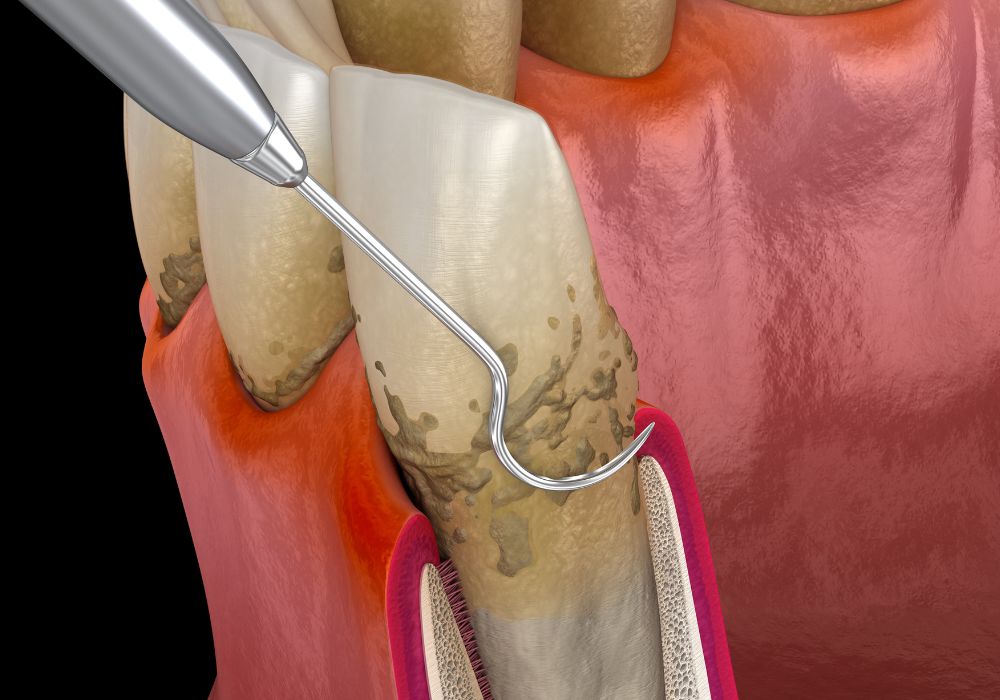

Dans la grande majorité des cas, le traitement débute par une phase non chirurgicale, appelée détartrage et surfaçage radiculaire.

Ce soin minutieux vise à éliminer la plaque et le tartre accumulés sous la gencive, là où la brosse à dents ne peut pas accéder.

Utilise des instruments ultrasoniques et manuels très fins,

Permet de nettoyer en profondeur les racines des dents et de favoriser la réadhésion de la gencive.